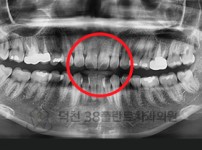

치료전후